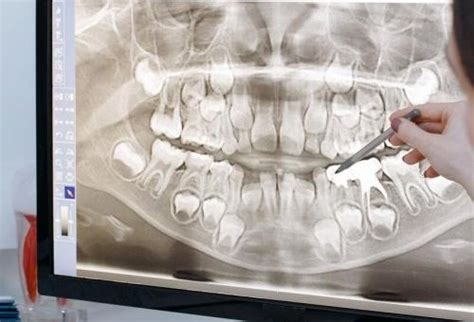

¿Qué Detecta una Ortopantomografía?

Además de detectar su presencia, la ortopantomografía permite evaluar su extensión.

En una radiografía panorámica se pueden ver todas las piezas dentales, incluyendo aquellas que aún no han erupcionado completamente.

Gracias a su capacidad para identificar una amplia gama de problemas dentales y maxilofaciales, las radiografías panorámicas son un pilar en la planificación y diagnóstico odontológico. En conjunto, una radiografía panorámica ofrece una visión detallada que permite diagnosticar diversas condiciones dentales, desde caries hasta problemas de las encías y anomalías en la posición de los dientes.